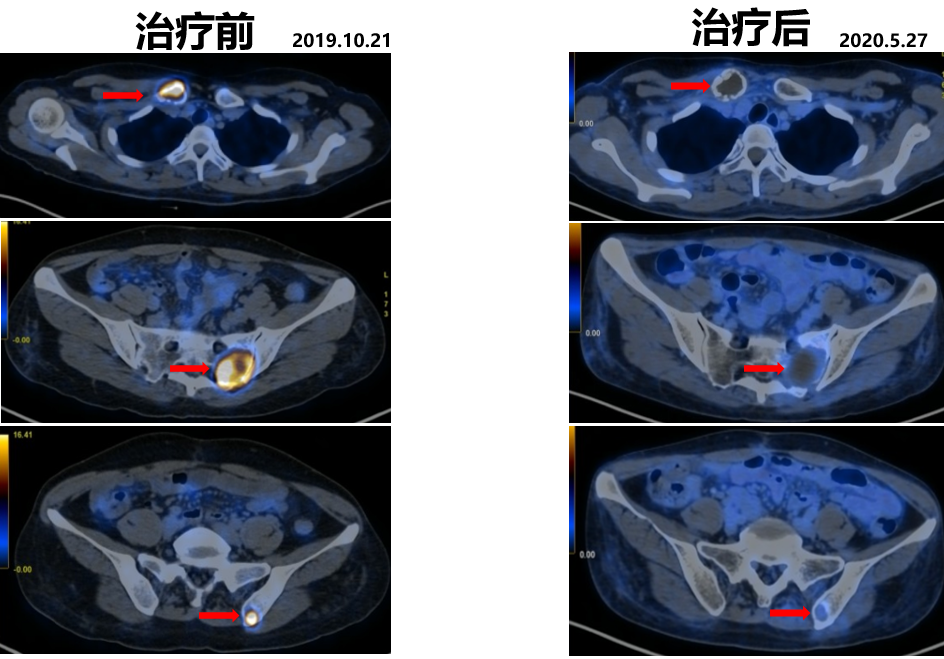

2019.10.21开始舒尼替尼50 mg po QD治疗(4/2方案)。

2020.05.27复查PET-CT病灶稳定,代谢较治疗前明显减低。影像学评估SD。

△舒尼替尼治疗后病灶稳定,代谢较治疗前明显减低